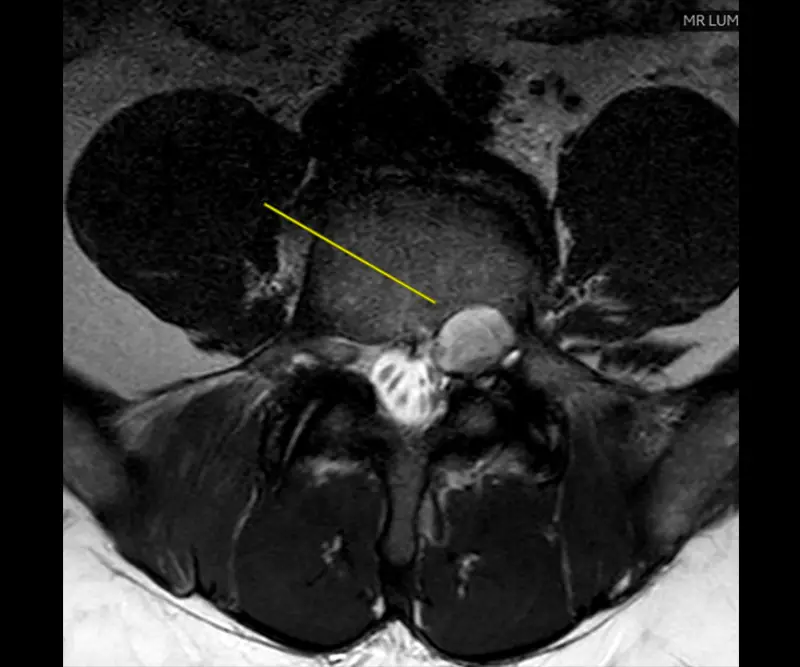

Pre-operative MRI showing severe spinal stenosis at L4-L5.

He also had severe spinal stenosis at the L4-L5 level which was causing nerve compression of all the nerves that go into the lumbar spine. Both conditions individually are relatively common but what’s uncommon is the combination of them. Usually a patient has lumbar stenosis, and someone has a spinal tumor. It’s very rare to have both come together at adjacent levels.